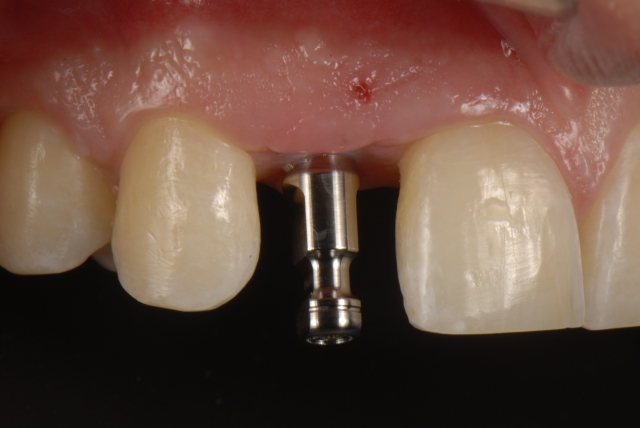

Single-tooth implants in the esthetic zone usually require a provisional restoration. The fabrication of a single-tooth implant-supported restoration requires a careful step-by-step approach to deliver a restoration that will assist the process of soft-tissue sculpting.

Here is a multi-step process showing the fabrication sequence of a screw-retained single-tooth implant provisional restoration of a lateral incisor.